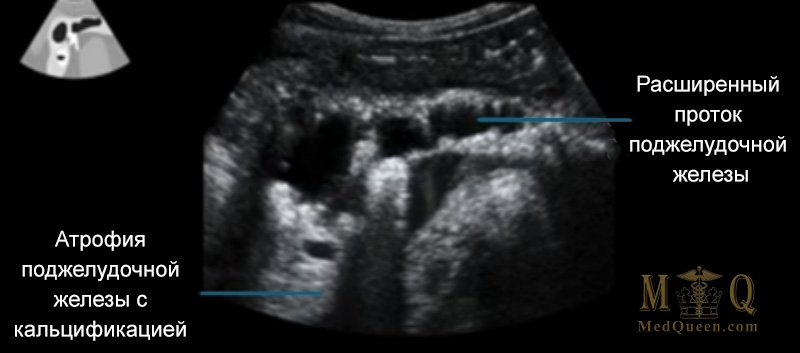

Хронический панкреатит характеризуется развитием атрофии, фиброза, кальцификацией тканей поджелудочной железы, что вызывает необратимые изменения.

Хронический панкреатит